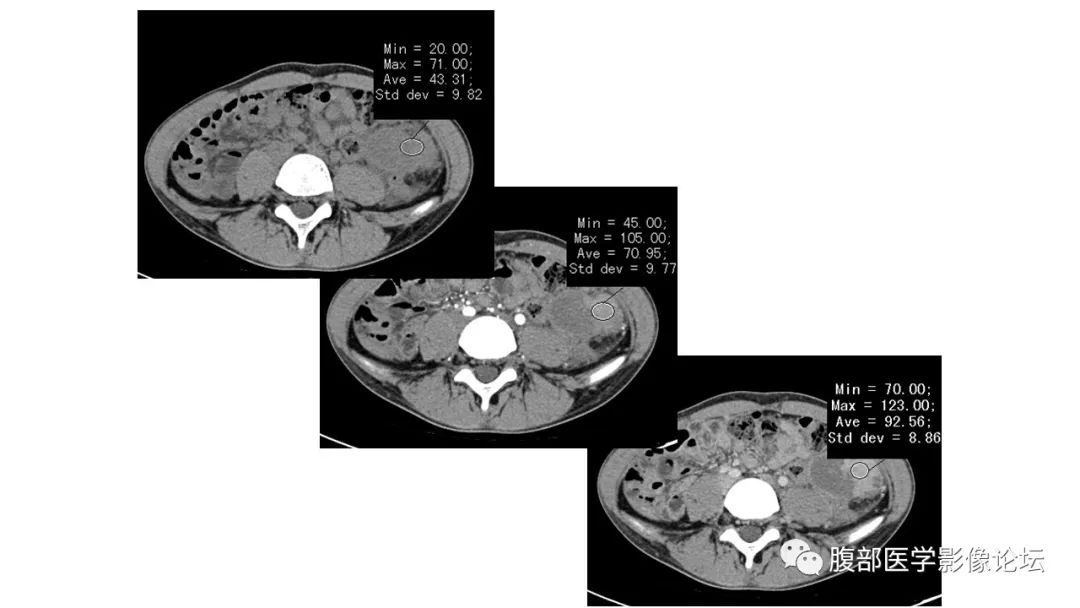

1.张文坦:左侧髂窝肿块,卵圆形,静脉汇入脾静脉,增强部分有强化,无强化区弥散高信号,部分可见暗化,周围渗出比较厉害,比较年轻,急性病程,炎性指标明显高,考虑副脾扭转部分梗死出血。鉴别IMT一般形态比较不规则,囊变坏死区范围小。 医学百科网 | YxBaike.Com

2.腹腔囊实性病灶,有脾静脉迂曲扩张,实性成份明显延迟强化,支持副脾。急腹症,提示扭转可能。囊液DWI高信号,表皮样囊肿? 医学百科网 | YxBaike.Com

综合考虑副脾伴表皮样囊肿扭转。